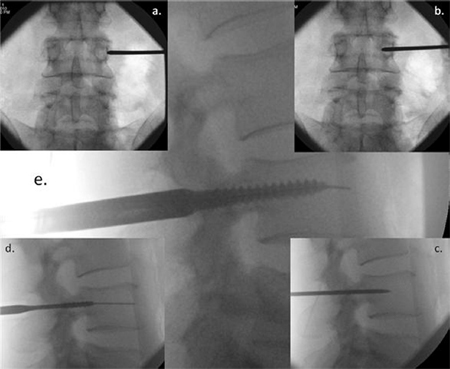

Fig. 2. Image intensifier radiographs of the percutaneous screw insertion technique showing: (a) anterior/posterior (AP) view of the Jamshidi needle docked onto the lateral

aspect of the pedicle – the ''3 o'clock position''; (b) AP view of advancement of the needle 20 mm to 25 mm into the vertebral body; (c) lateral view, checking the position of

the Jamshidi needle; (d) lateral view, the K-wire and tapping of the pedicle; and (e) lateral view, insertion of the pedicle screw.